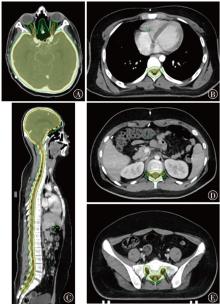

目的探索质子调强放疗(IMPT)、光子固定野调强放疗(IMRT)以及光子螺旋断层放疗(TOMO)技术应用于儿童全中枢神经系统肿瘤照射的剂量学特点。方法以1例山东省肿瘤防治研究院(山东省肿瘤医院)临床诊断为非典型畸胎样/横纹肌样瘤、脊膜转移、脑膜转移,行全脑全脊髓放疗(CSI)的14岁儿童患者靶区为例,根据靶区的临床处方和危及器官(OAR)的限值要求,分别设计IMPT、IMRT和TOMO计划。对各计划靶区的适形指数(CI)、均匀性指数(HI)和梯度指数(GI),以及正常组织的剂量体积指标进行评估,对比3类计划的剂量学特点。结果IMPT计划的CI(0.71)、HI(0.05)和GI(3.13)均与IMRT计划(0.80、0.08、3.14)相当,TOMO计划的HI(0.03)、GI(2.54)较优,且均在临床接受范围内。IMPT计划中并行器官受照剂量低于IMRT和TOMO计划;IMPT计划中双肺V5为2.9%,IMRT为37.6%,TOMO为43.5%;IMPT计划的肝脏Dmean为0.01 Gy(RBE),IMRT计划为6.12 Gy,TOMO计划为6.39 Gy;IMPT计划中膀胱、直肠、股骨头均没有受量,而在IMRT和TOMO计划中均有低剂量辐射。对于毗邻靶区和包含在靶区内的串行器官,IMPT计划中脊髓和脑干的Dmax分别为39.89和39.88 Gy(RBE),IMRT计划分别为39.43 和38.59 Gy,TOMO计划分别为38.41和37.69 Gy。IMPT计划中低剂量区显著优于光子放疗计划,其中患者体内10%的处方剂量区域所占的绝对体积IMPT计划较IMRT计划减少了70.10%,较TOMO计划减少了76.96%;30%的处方剂量体积IMPT计划较IMRT计划减少了53.49%,较TOMO计划减少了62.51%;50%的处方剂量体积IMPT计划较IMRT计划减少了39.06%,较TOMO计划减少了42.23%。结论在儿童CSI中,IMPT计划的低剂量区与并行OAR受照剂量显著少于IMRT和TOMO计划。3种计划的CI、HI和GI均能满足临床要求。对于毗邻靶区和包含在靶区内的串行器官,IMPT计划的Dmax可能比IMRT和TOMO计划剂量更高。

ObjectiveTo explore the dosimetric characteristics of intensity modulated proton therapy (IMPT),intensity modulated radiation therapy (IMRT) and tomotherapy (TOMO) techniques applied in the irradiation of pediatric whole central nervous system tumors.MethodsTaking the target area of a 14-year-old pediatric patient clinically diagnosed with atypical teratoid/rhabdomyoid tumor,meningeal metastasis by Shandong Cancer Hospital and Institute,and undergoing craniospinal irradiation (CSI) as an example,IMPT,IMRT and TOMO plans were designed respectively based on the clinical prescription of the target area and the limit requirements of organs at risk (OARs). The conformal index (CI),homogeneity index (HI) and gradient index (GI) of each planning target volume,as well as the dose volume index of normal tissues,were evaluated to compare the dosimetric characteristics of the three types of plans.ResultsThe CI (0.71),HI (0.05) and GI (3.13) of the IMPT plan were comparable to those of IMRT plan (0.80,0.08,3.14). The HI (0.03) and GI (2.54) of the TOMO plan were excellent,which were all within the clinically acceptable range. The irradiation dose to parallel organs in the IMPT plan was lower than that in the IMRT and TOMO plan. In the IMPT plan,V5of lungs was 2.9%,IMRT plan was 37.6%,and TOMO plan was 43.5%. The Dmeanof liver in the IMPT plan was 0.01 Gy(RBE),IMRT plan was 6.12 Gy,and TOMO plan was 6.39 Gy. In the IMPT plan,none of the bladder,rectum,and femoral head received the dose,while there was low-dose radiation in both IMRT and TOMO plan. For serial organs adjacent to and within the target area,the Dmaxof spinal cord and brainstem in IMPT plan was 39.89 and 39.88 Gy(RBE),respectively; in IMRT plan,they were 39.43 and 38.59 Gy,respectively; and in TOMO plan,they were 38.41 and 37.69 Gy,respectively. The low-dose area in the IMPT plan was significantly better than the photon radiotherapy plans. Among them,the absolute volume IMPT plan occupied by 10% of the prescribed dose area in the patient's body was reduced by 70.10% compared with IMRT plan and 76.96% compared with TOMO plan; the 30% prescribed dose volume IMPT plan was reduced by 53.49% compared with IMRT plan and 62.51% compared with TOMO plan; the 50% prescribed dose volume IMPT plan was reduced by 39.06% compared with IMRT plan and 42.23% compared with TOMO plan.ConclusionsThe IMPT plan demonstrated significantly reduced low-dose exposure and lower doses to parallel OARs compared to both IMRT and TOMO plans in pediatric CSI. The CI,HI and GI of the three plans can all meet the clinical requirements. However,for serial organs adjacent to and within the target area,the Dmaxof the IMPT plan may be higher than that of IMRT and TOMO plans.